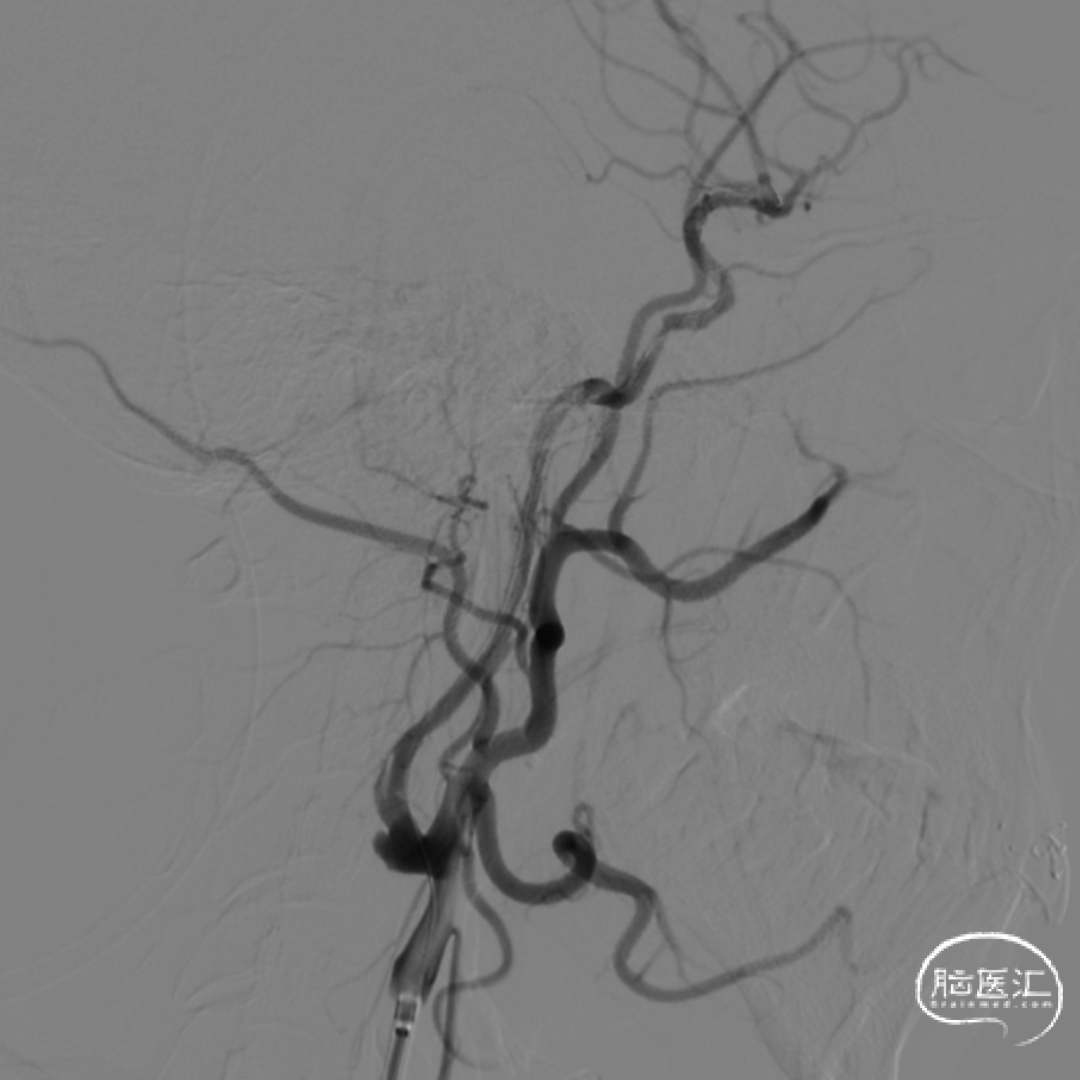

沿4.0×30mm Syphonet®取栓支架输送导丝送入3.0×12mm SacSpeed®球囊扩张导管,自C1-C7段分次扩张,每次释压后跟进中间导管至C5段,复查造影显示血流通畅。

造影提示C5-C6段仍有残余狭窄。于是利用SacSpeed®球囊扩张导管收回部分Syphonet®取栓支架,在狭窄处直接扩张。

撤回SacSpeed®球囊扩张导管,复查造影。

前送5F Tethys®中间导引导管至大脑中动脉M1段,在负压抽吸下将Syphonet®取栓支架回收至中间导管内,并缓慢回撤Tethys®中间导引导管至C5段,持续负压下将Syphonet®取栓支架撤出,抽吸注射器内无明显血栓,支架上可见1mm血栓碎片,术中观察患者意识、肢体功能较前无明显变化。